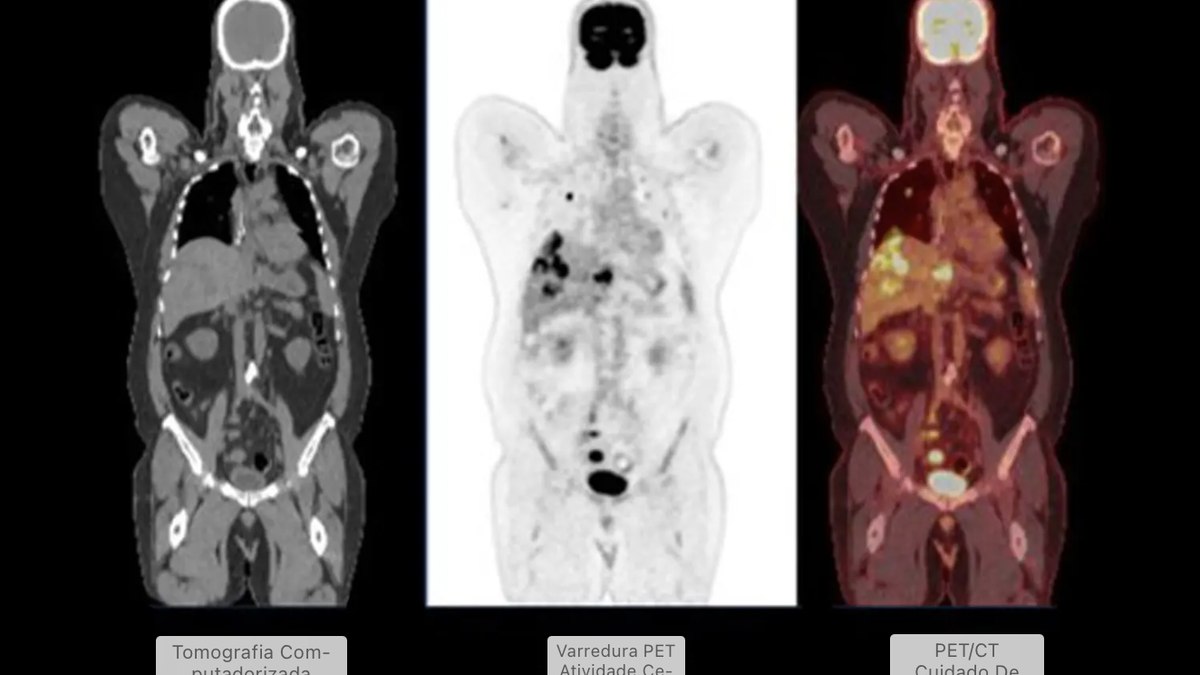

A questão é que o mecanismo de ação desses medicamentos também pode afetar como o corpo absorve o marcador radioativo FDG, usado nas tomografias PET. Esse marcador identifica células com metabolismo acelerado, como as cancerígenas. Quando o padrão de absorção é alterado, os exames podem mostrar “pontos quentes” enganosos, fazendo parecer que há inflamação ou tumor onde não existe.